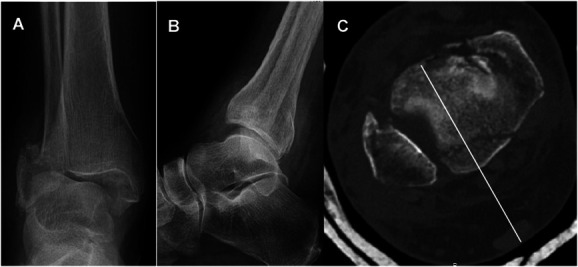

后踝骨骨折(PMFs)(OTA 43B1.1)经常与腓骨、内侧踝骨和胫骨远端骨折同时发生,很少单独出现。PMF 会影响踝关节臼的对齐和巩膜的稳定性。用于固定PMF的技术包括通过后外侧或后内侧方法进行开放复位内固定,或进行前后螺钉固定。对于选定的微移位或无移位的后踝骨骨折,我们开发了一种经皮技术,通过跟腱插入后至前插管螺钉。本文对该技术进行了描述,并回顾了一系列临床案例。

Posterior malleolus fractures (PMFs) (OTA 43B1.1) are frequently seen in combination with fractures of the fibula, medial malleolus, and distal tibia; they can rarely be seen in isolation. PMFs affect the alignment of the ankle mortise and the stability of syndesmosis. Techniques described for fixation of PMFs include open reduction internal fixation through a posterolateral or posteromedial approach or anterior-to-posterior screw fixation. For selected minimally displaced or nondisplaced fractures of the posterior malleolus, we developed a percutaneous technique through the Achilles tendon for the insertion of a posterior-to-anterior cannulated screw. The technique is described, and a clinical series is reviewed.